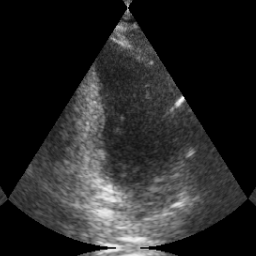

Transthoracic echo is one of the most common means of cardiac studies in the clinical routines. During the echo exam, the sonographer captures a set of standard cross sections (echo views) of the heart. Each 2D echo view cuts through the 3D cardiac geometry via a unique plane. Consequently, different views share some limited information. In this work, we investigate the feasibility of generating a 2D echo view using another view based on adversarial generative models. The objective optimized to train the view-conversion model is based on the ideas introduced by LSGAN, PatchGAN and Conditional GAN (cGAN). The size and length of the left ventricle in the generated target echo view is compared against that of the target ground-truth to assess the validity of the echo view conversion. Results show that there is a correlation of 0.50 between the LV areas and 0.49 between the LV lengths of the generated target frames and the real target frames.